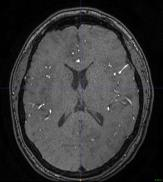

The use of deep learning techniques for 3D brain vessel image segmentation has not been as widespread as for the segmentation of other organs and tissues. This can be explained by two factors. First, deep learning techniques tend to show poor performances at the segmentation of relatively small objects compared to the size of the full image. Second, due to the complexity of vascular trees and the small size of vessels, it is challenging to obtain the amount of annotated training data typically needed by deep learning methods. To address these problems, we propose a novel annotation-efficient deep learning vessel segmentation framework. The framework avoids pixel-wise annotations, only requiring patch-level labels to discriminate between vessel and non-vessel 2D patches in the training set, in a setup similar to the CAPTCHAs used to differentiate humans from bots in web applications. The user-provided annotations are used for two tasks: 1) to automatically generate pixel-wise labels for vessels and background in each patch, which are used to train a segmentation network, and 2) to train a classifier network. The classifier network allows to generate additional weak patch labels, further reducing the annotation burden, and it acts as a noise filter for poor quality images. We use this framework for the segmentation of the cerebrovascular tree in Time-of-Flight angiography (TOF) and Susceptibility-Weighted Images (SWI). The results show that the framework achieves state-of-the-art accuracy, while reducing the annotation time by up to 80% with respect to learning-based segmentation methods using pixel-wise labels for training